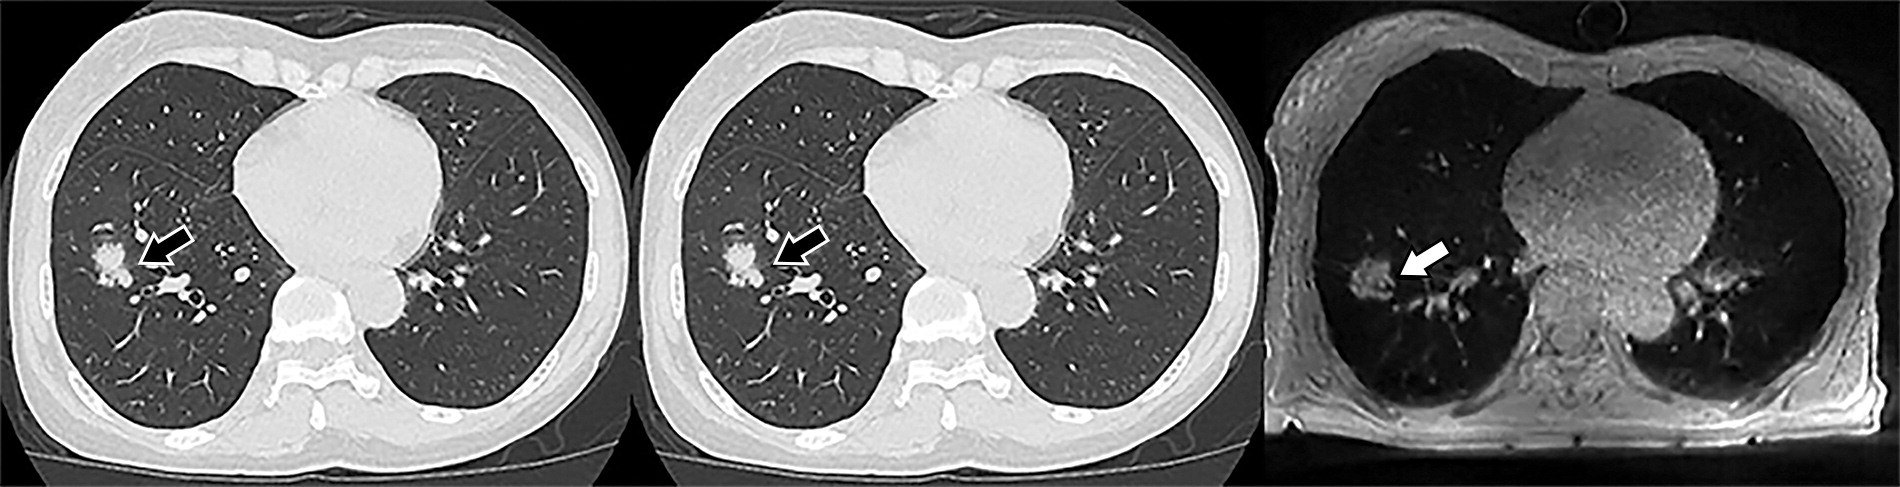

下图展示了一个67岁男性的三种肺部影像。该结节如箭头所指,被诊断为实性结节;Lung-RADS分类为4B类。

23a7b5ff13c5ca1bbaa71d8fdaf4d191.jpeg